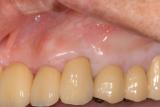

根面被覆 | |||||||||||

| 歯がしみていました、詰め物で治療しても数年で変色して再治療が必要になり、だんだん歯がなくなります。退縮した歯ぐきを再生して歯がしみるのを改善しました。 |

【術前】 |

【術後】 |